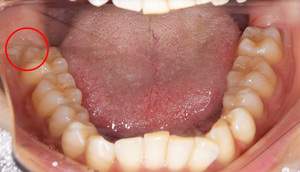

口腔内写真

麻布十番歯科での右下の親知らずが真横に生えている症例の口腔内写真

右下の親知らずが気になると言う主訴でいらっしゃった患者様です。

レントゲンで確認すると、真横にはえており、さらに、下歯槽神経と接触しているようにみえます。